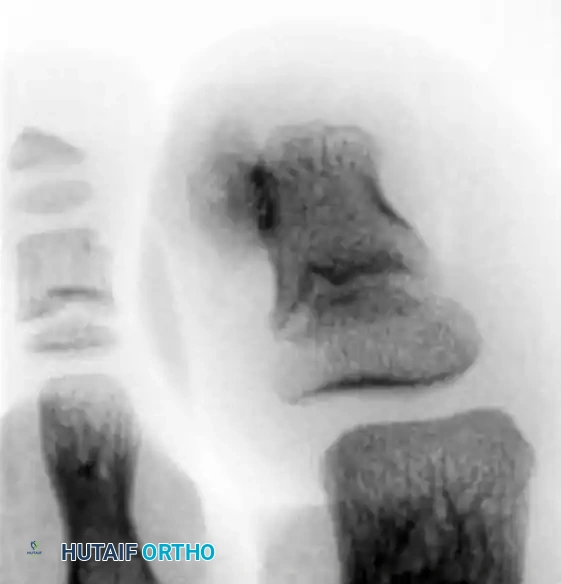

Radiographic Imaging:

Routine weight-bearing radiographs of the foot may completely miss the exostosis because standard anteroposterior (AP) and lateral techniques do not adequately isolate or emphasize the distal phalanx.

⚠️ Surgical Warning: Imaging Pitfalls

Never rely solely on standard foot series to rule out a subungual exostosis. Radiographs must be taken at oblique angles, specifically targeting the distal phalanx, and should be magnified. A true lateral of the isolated digit is the most sensitive view for identifying the dorsal bony outgrowth.